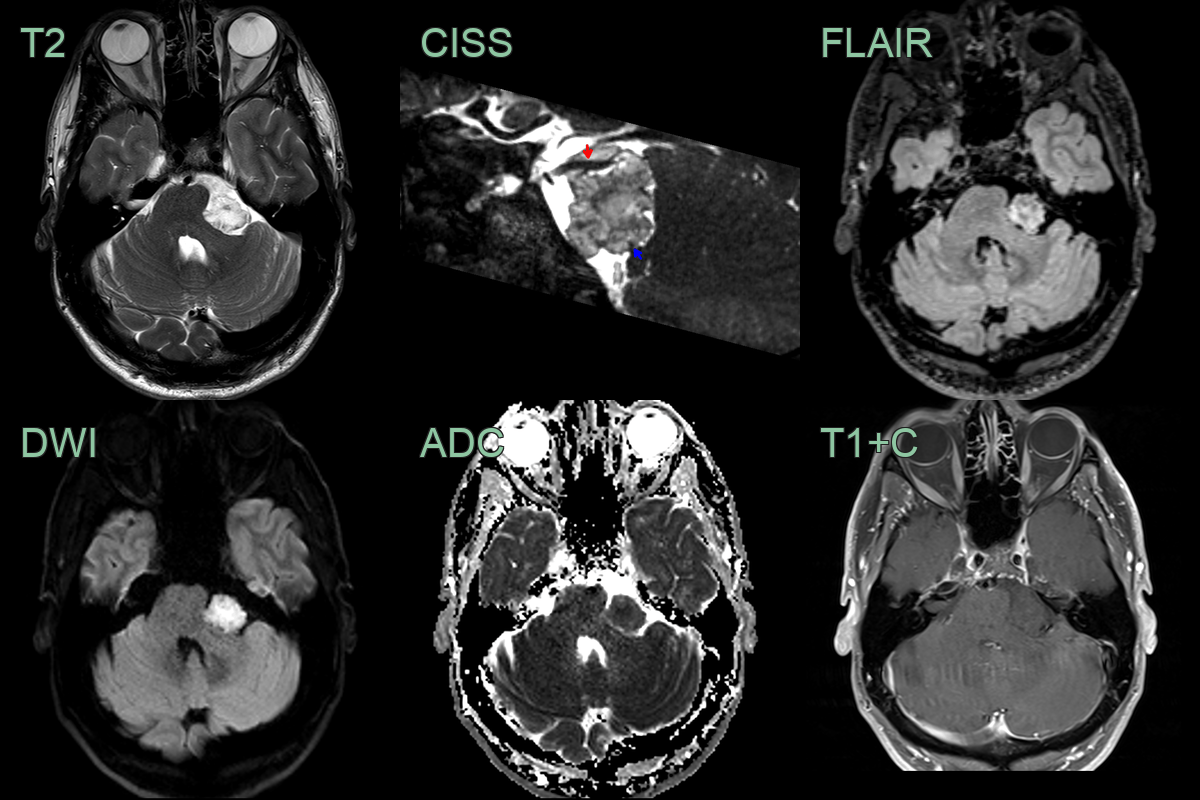

- 60-year-old patient present with ataxia and poor left-sided hearing.

- MRI showed a T2-hyperintense non-enhancing lobulated lesion with low ADC values in the left side of the posterior fossa, encasing the 7th and 8th nerve complexes.

- There was significant mass effect on the cerebellum (presumably relevant to the ataxia) but there was no oedema, indicating that this lesion has grown slowly.

- MRI:

- T1: Hypointense to isointense

- T2: Hyperintense

- FLAIR: Heterogeneous signal intensity

- DWI: Marked restriction (key diagnostic feature)

- No enhancement with gadolinium

- "Popcorn" appearance on DWI due to lamellated keratin